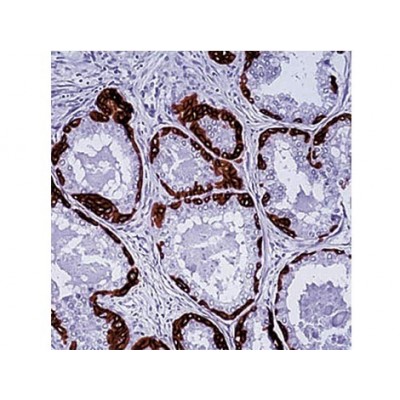

Positive Control: Skin

Specificity: This antibody is specific to cytokeratin 13, 14, 15 and 16. This antibody stains squamous carcinomas and adenosquamous carcinomas but does not stain adenocarcinoma. This antibody is useful in differential staining of squamous carcinomas from adenocarcinomas and to differentiate benign and malignant tumors of prostate glands.